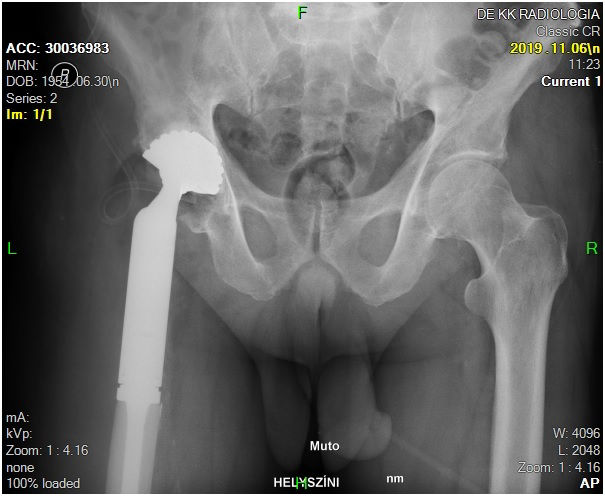

29 éves pályám során közel ezer térdprotézist és több mint kétezer csípőprotézist ültettem be. Az utóbbi években egyre több, nagy műszer igényű, összetett protézis revíziós műtétet végzek.

Fő érdeklődési köröm a biomechanika, műszerfejlesztés, új műtéti technikák kidolgozása és a nagyízületi endoprotetika.